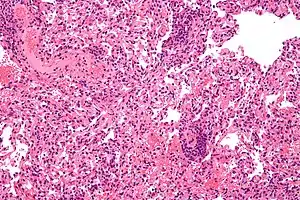

| Micrograph showing lung transplant rejection. Lung biopsy. H&E stain. | |

Diagnosis of acute rejection relies on clinical data—patient signs and symptoms but also calls on laboratory data such as blood or even tissue biopsy. The laboratory pathologist generally seeks three main histological signs: (1) infiltrating T cells, perhaps accompanied by infiltrating eosinophils, plasma cells, and neutrophils, particularly in telltale ratios, (2) structural compromise of tissue anatomy, varying by tissue type transplanted, and (3) injury to blood vessels. Tissue biopsy is restricted, however, by sampling limitations and risks/complications of the invasive procedure.[31][32][33] Cellular magnetic resonance imaging (MRI) of immune cells radiolabeled in vivo might—similarly to Gene Expression Profiling (GEP)—offer noninvasive testing.[34][35]